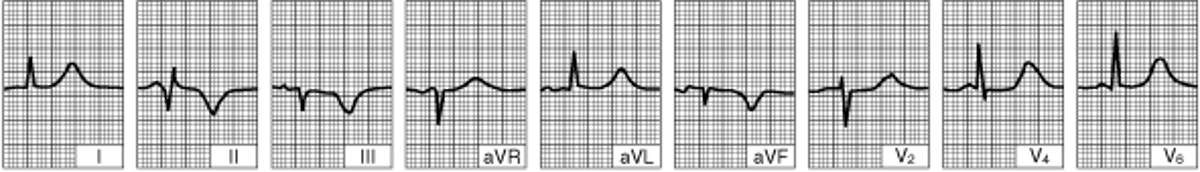

Нижний инфаркт (диафрагмальный) левого желудочка (несколько суток с момента развития заболевания)

Изоэлектричное расположение сегмента ST. Глубокие зубцы Q в отведениях II, III, aVF указывают на сформировавшийся рубец.